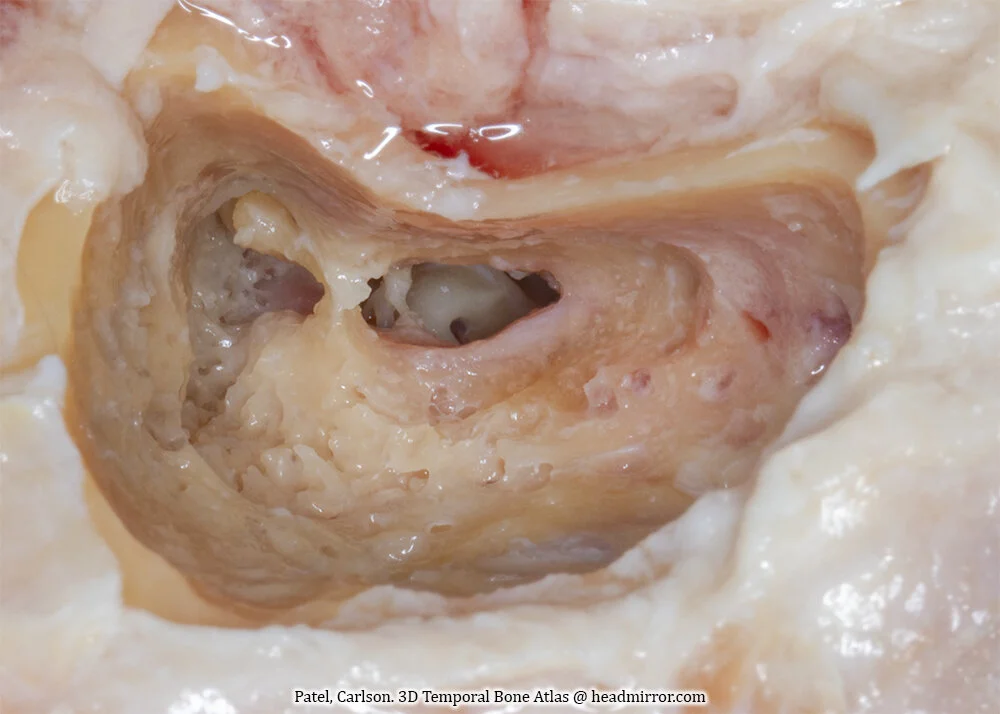

CHAPTER 8: Cochlear Implantation

3D Temporal Bone Atlas

Cochlear Implantation